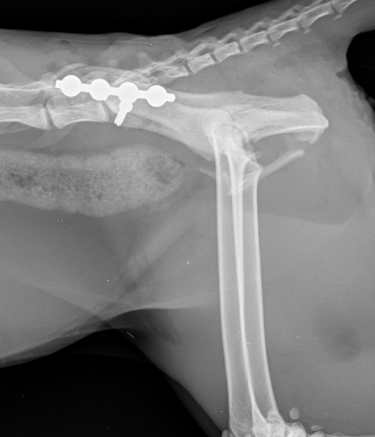

To address her injuries, a 2.4mm screw was placed to stabilize the sacroiliac joint, and a 2mm SOP plate with two proximal and two distal screws was used to reduce the ilial fracture (Figs. 3 and 4).

Fig. 4